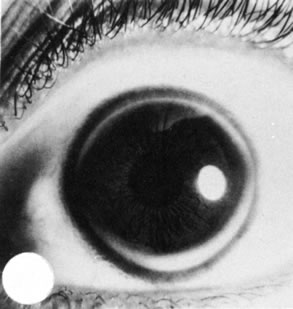

Fig. 5. Peters' syndrome complicated by buphthalmos. The corneal anterior segment of the right eye has expanded because of the influence of increased intraocular pressure on scleral tissue that is still elastic in young people.